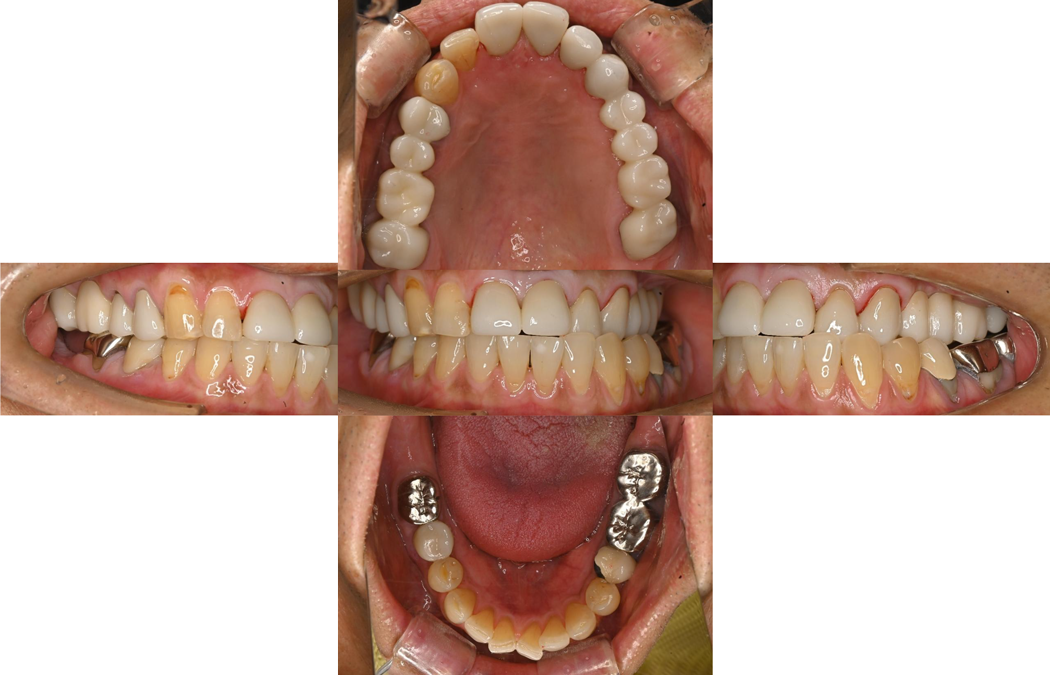

治療予後

治療終了後は、顎関節の不具合もなく、患者様も非常に満足してくださいました。